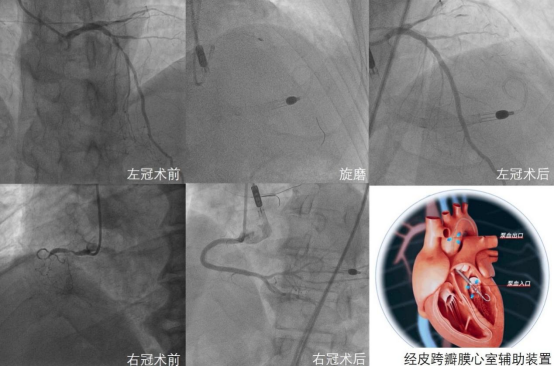

术中,心血管团队经左股动脉置入国产经皮跨瓣膜心室辅助装置。首先,在团队研发的冠状动脉CTA人工智能可视化系统指导下,开通慢性完全闭塞的右冠状动脉并置入支架,之后对左冠状动脉病变进行充分旋磨预处理后完成血运重建。手术历时4小时,患者全程血流动力学稳定。术后即刻撤除经皮跨瓣膜心室辅助装置,患者恢复良好,并于术后第三日出院。